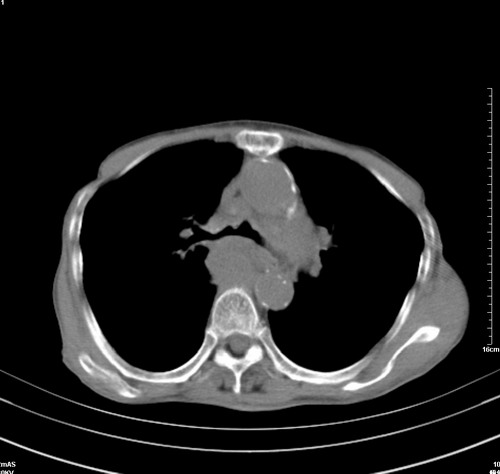

病人,女,79岁,主要因腹疼二月入院,彩超,肝,胆,脾,未见异常,胸透上消化道造影未见异常,化验白细胞增高,内科医生让做胸部ct检查,因为熟人多做了腹部(外科会诊考虑胆囊炎).现ct片如下请假各位战友.

中后纵隔占位,气管、食道受压、变形、移位。恶性可能性大。

考虑:中后纵隔转移瘤可能性大,主动脉硬化。

1 气管旁、隆突下淋巴结明显肿大,肝左叶外侧段低密影,都考虑转移。

纵隔淋巴结肿大,考虑转移而来

肺癌,纵隔淋巴结转移,肝左叶病变考虑为转移病灶。

后中纵隔团块影,伴气管、食道受压移位,首先考虑转移瘤,肝s5段低密度灶。建议增强检查,另外其结肠是否有问题请提供,右肺部分肺叶局限含气增多,考虑局限肺气肿。

建议强化检查,考虑纵隔型肺癌,小细胞可能性大。

后中纵隔团块影,伴气管、食道受压移位,首先考虑转移瘤,肝表现同11773。

后中纵隔淋巴结肿大,首先考虑转移瘤。